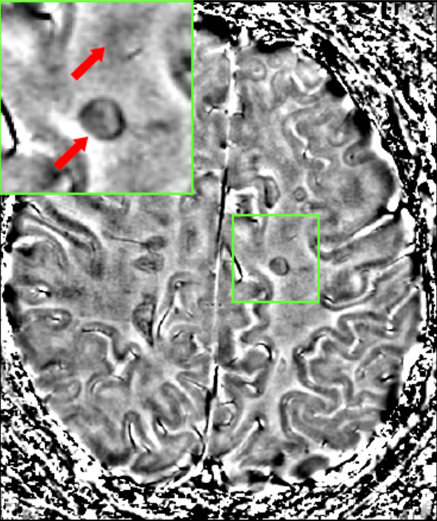

Aquesta malaltia és la causa més freqüent d’incapacitat neurològica en adults joves. Es caracteritza per lesions inflamatòries localitzades a la substància blanca (encara que un 5% de les lesions inflamatòries es localitzen a la substància grisa).

- En la imatge podem observar múltiples lesions cerebrals produïdes per l’esclerosi.